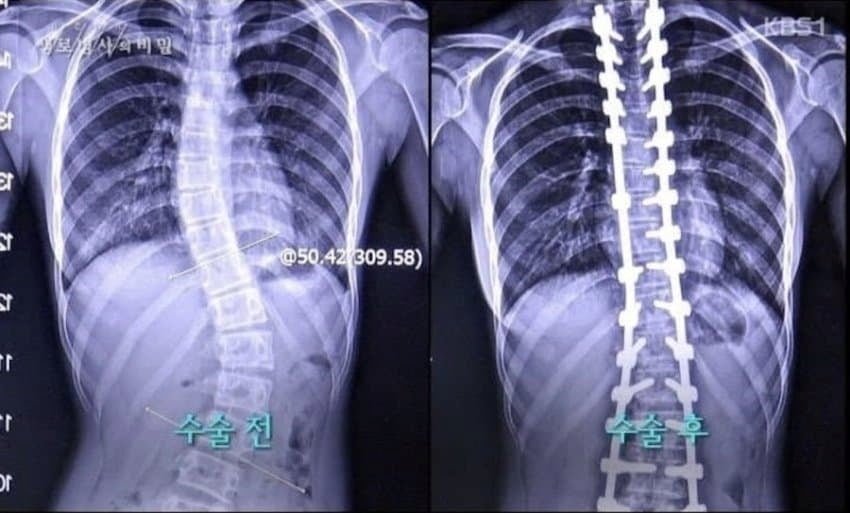

한 고등학생이 척추측만증으로 괴로워하며 응급실을 자주 드나드는 충격적인 실화가 공개되었다. 17세의 한지민은 심각한 병세 때문에 여러 번의 병원 방문을 피할 수 없었다. 엑스레이 검사 결과, 그녀의 척추는 심각하게 휘어 있었고, 수술이 불가피하다는 의사의 진단을 받았다.